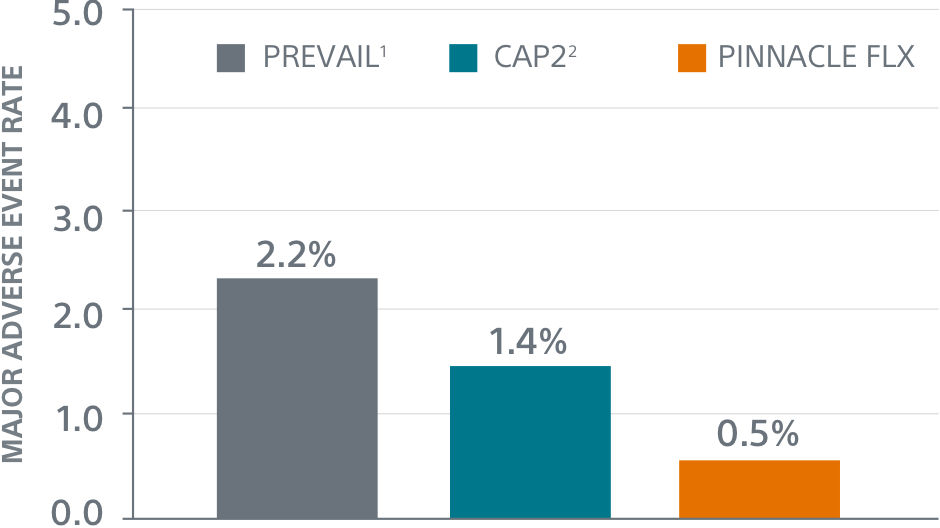

PINNACLE FLX

Study Design

- 400 patient, 29 US site, single arm, non-randomized trial evaluating WATCHMAN FLX for non-inferiority to safety and efficacy performance goals based on the WATCHMAN™ device.

- Follow-up: 45 days (+TEE), 6 months, 12 months (+TEE), 18 months, and 24 months

- Patient Characteristics: Average CHA2DS2-VASc of 4.2±1.5, Average HAS-BLED of 2.0±1.0

- Post Implant Drug Regimen: NOAC/ASA for 45 days, Clopidogrel/ASA to 6 months, ASA post 6 months

- Primary Safety Endpoint: All-cause death, ischemic stroke, systemic embolism, or device- or procedure-related adverse events requiring surgery or major endovascular intervention within 7 days following the procedure or by hospital discharge, whichever is later.

- Primary Efficacy Endpoint: The rate of effective LAA closure defined as any peri-device flow ≤5mm demonstrated by TEE at 12 months

- Secondary Efficacy Endpoint: The occurrence of ischemic stroke or systemic embolism at 24 months from the time of enrollment

- Inclusion/exclusion criteria is consistent with WATCHMAN clinical study inclusion/exclusion criteria. Patients must be eligible for short-term NOAC vs warfarin in previous clinical studies.

Primary Safety Endpoints

Primary Efficacy Endpoints

The rate of effective LAA closure defined as any peri-device flow ≤5mm demonstrated by TEE at 12 months.

** Performance goal pased on the rates observed in PREVAIL(1) and CAP2(2), minus a clinically relevant delta